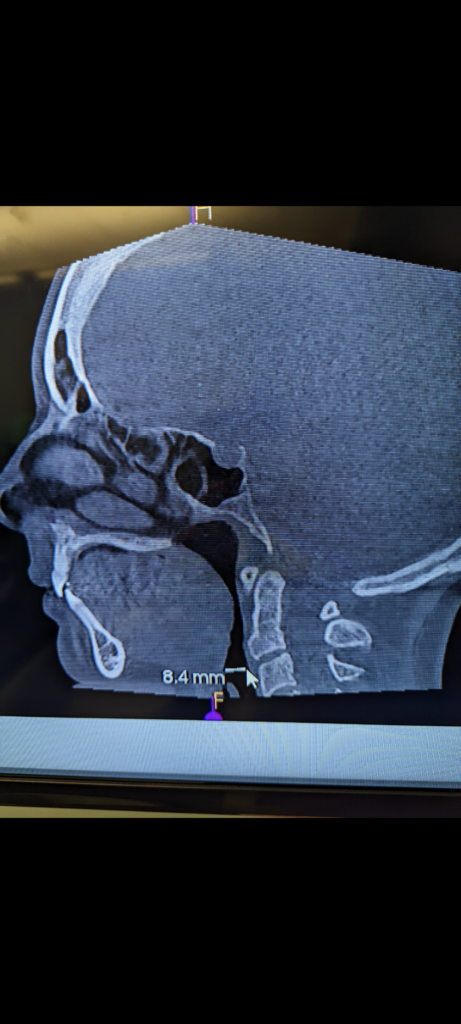

The CT scan measured my airway at 8.4 MM. Average female pharynx is 33 MM.